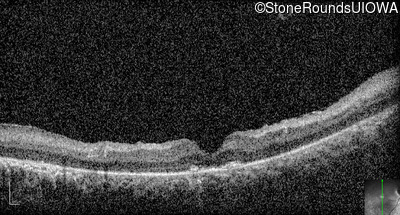

Age at visit: 15 years

OD OS

This 15 year old male has had very poor vision and nystagmus since the first year of life.